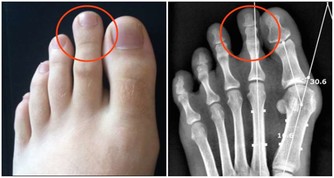

改善肝臟功能,有助於抵禦風濕性疾病和痛風